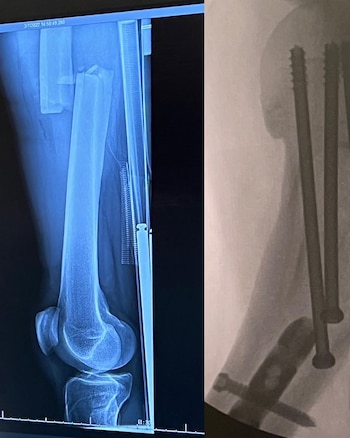

En una publicación en su Instagram personal, Tony mostró una radiografía para informar la fractura en la pierna que sufrió al caerse y contó que debieron ponerle tornillos en la zona. “Me rompí el codo hace 20 años y logré recuperarme por completo; esta recuperación de una fractura de fémur será mucho más difícil debido a su gravedad y mi edad. Pero estoy listo para el desafío”, redactó en un mensaje que abrió la puerta a los interrogantes sobre su futuro.

“He dicho muchas veces que no dejaré de patinar hasta que esté físicamente incapacitado. Una pierna rota probablemente será la mayor prueba. Volveré... tal vez no a plena capacidad, pero renuncié a esa noción hace años cuando me acercaba a la “mediana edad”. Gracias a mi inquebrantable y tolerante familia, y a todos ustedes, por el amor y el apoyo a lo largo de los años. No estaría aquí sin ti. Nos vemos en el otro lado”, planteó mostrando su fortaleza anímica para combatir esta delicada lesión.

Este miércoles, Hawk se encargó de hacer una actualización con una foto de él en la camilla mientras recibía uno de los medicamentos y una frase: “Soy un chico paciente”. La leyenda del skate arrancó la extensa recuperación que le demandará esta fractura de fémur. Aunque ya mostró su ímpetu por progresar: en otras imágenes se mostró caminando lentamente en los pasillos del hospital o simplemente de pie al lado de su cama.